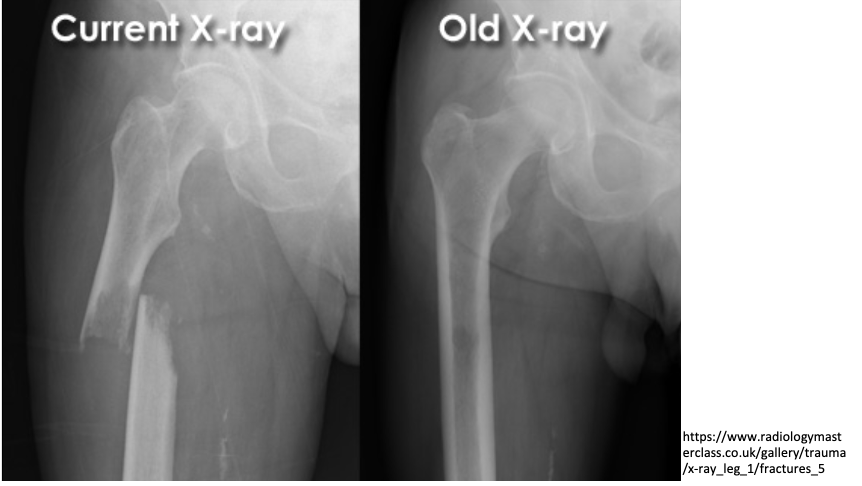

intra-capsular vs extra-capsular classification

intracapsular: involving the head or neck of femur

fracture through neck of femur (most common in younger patients)

mechanism of trauma: axial loading during high force trauma (feet on dashboard)

if hip is abducted position

extracapsular: involving the femur excluding head or neck of femur

fracture through the trochanters

comminuted fracture (radiolucent) of the left proximal femur

intertrochanteric fracture (between the two trochanters)

extra-capsular classification

intracapsular fracture

65 year old male:

fall onto left side while getting out of bed

AP radiograph of the hip

Prior DXR (bone density) scan showed marked osteoporosis

(extracapsular classification)

radiolucent intertrochanteric fracture of the left proximal femur

or

radiolucent oblique fracture through the greater trochanter and neck of the femur on the left side